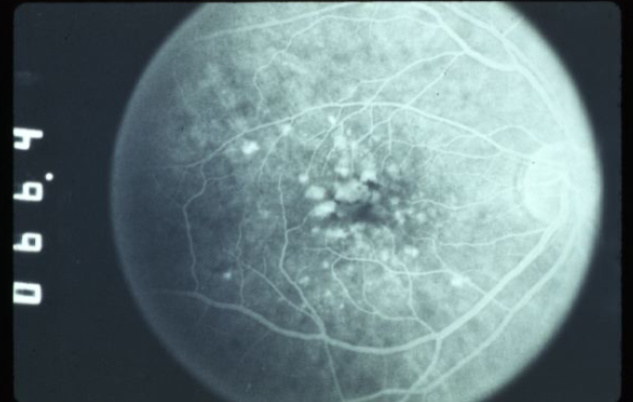

FA shows early, well defined focal hyperfluorescence w/o leakage

FA demonstrates early hyperfluorescence that does not leak & fades midway through

drusen

drusen

hard drusen

soft drusen

soft drusen

soft drusen

soft drusen